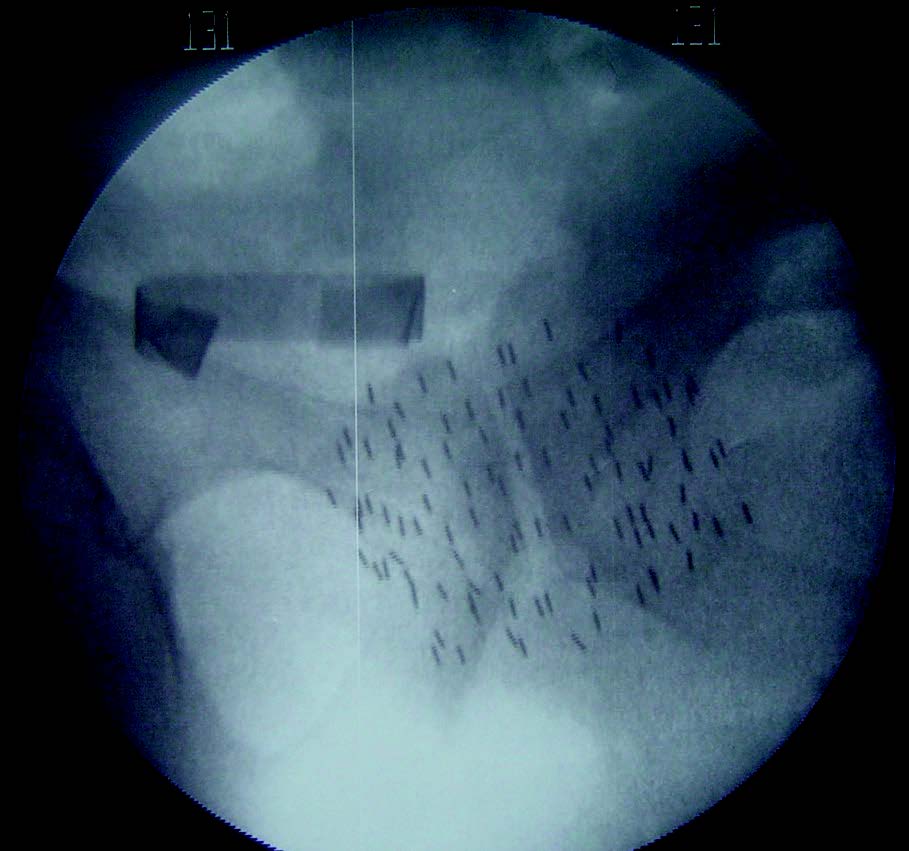

Cette technique consiste à fixer dans la prostate des sources radioactives. L’irradiation est alors très localisée, permettant une augmentation substantielle de la dose.

Classiquement, l’iode 125 était utilisé sous forme de grains, ceux-ci restant définitivement dans la glande, mais perdant leur radioactivité entre 4 et 6 mois.

Si l’on opte pour la curiethérapie dite à haut débit de dose, plus récente, la source radioactive est alimentée par des cathéters implantés dans la prostate. Selon les protocoles, entre 1 et 4 séances sont réalisées lors desquelles une dose de 5 à 10 Gy est délivrée en quelques minutes. Dans cette situation, la glande prostatique uniquement est irradiée.

Initialement utilisée seule, la curie­thérapie est maintenant employée en combinaison avec la RTE. Cette dernière délivre une dose intermédiaire (de 45 à 50 Gy ou équivalent) sur la prostate et les tissus périprostatiques, le complément étant apporté par la curiethérapie. Quand elle est associée à la RTE, celle-ci autorise, versus la RTE seule, une escalade de dose plus élevée et ce, sans majorer la toxicité rectale.